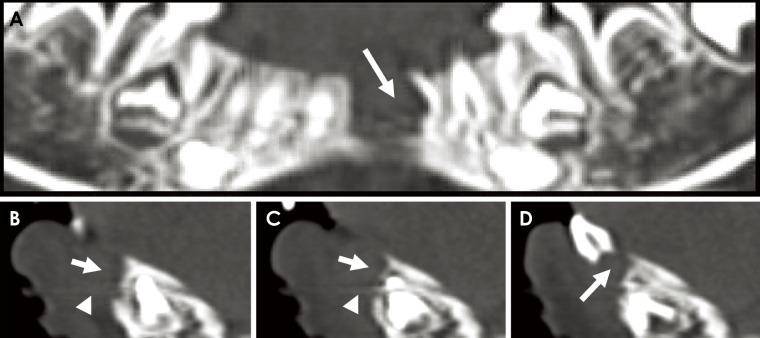

一名2岁女童的下颌骨中央巨细胞病变。

Central giant cell lesion of the mandible in a 2-year old girl.

Central giant cell lesions are rare, benign, osteolytic, pseudocystic, solitary, localized lesions that are common in the skeletal structure, but less so in the maxillofacial region. Furthermore, to perform panoramic radiography and cone-beam computed tomography, it is necessary to prepare patients properly and to position their heads carefully. However, this can be difficult in pediatric patients, who may be anxious. In this report, we describe the case of a central giant cell lesion of the mandible in a 2-year-old girl that was evaluated with multidetector computed tomography.

摘要

中央巨细胞病变是罕见的、良性的、溶骨性的、假性囊肿性的、孤立的、局限性病变,常见于骨骼结构,但在颌面部区域较少见。此外,要进行全景放射摄影和锥形束计算机断层扫描,需要妥善准备患者并仔细摆放其头部位置。然而,对于可能焦虑的儿科患者来说,这可能很困难。在本报告中,我们描述了一名2岁女孩下颌骨中央巨细胞病变的病例,该病例采用多排探测器计算机断层扫描进行了评估。